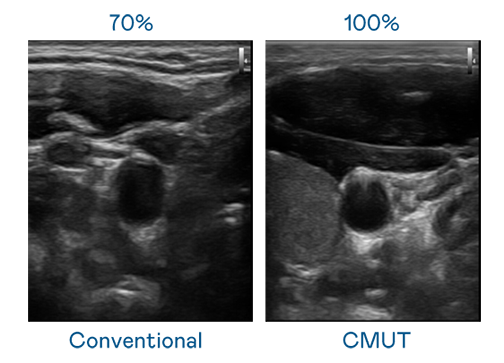

CMUT 技术是一种用电容式微机电元件来产生超音波讯号的技术。与传统 PZT 压电式技术相比,CMUT 频宽增加 30%,更宽频的超音波讯号让影像解析度大幅提升,是实现高影像品质医疗超音波扫描、促进精准医疗发展的关键技术。

大频宽带来超清晰影像

超音波影像的解析度高低,首先取决于探头能发出的讯号频宽。爱游戏官网 CMUT 可提供高清晰的超音波讯号,提供高频宽、高灵敏度、影像纹理细节更高的超音波影像,协助医护人员缩短影像判读时间及利用精准的医疗影像进行诊断。